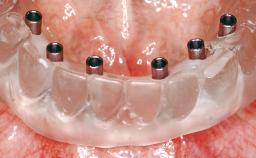

Conventional Loading of Eight Implants in the Maxilla and Final Restoration with a Full-Arch Gold-Ceramic FDP

A 35-year-old Caucasian female presenting with advanced periodontal disease involving both the maxillary and the mandibular dentition was referred for evaluation. The patient, a non-smoker in good general health, requested treatment for recurrent periodontal abscesses, tooth mobility, and discomfort during chewing, as well as restoration of her missing teeth with a fixed prosthesis to improve mastication and esthetics. All residual maxillary teeth exhibited plaque deposits, deep pockets, bleeding on probing, and class III mobility and were evaluated as hopeless. All residual mandibular teeth except tooth 37 could be maintained after periodontal therapy.

| # of Implants | 8 |

| Attachment | One-Piece |